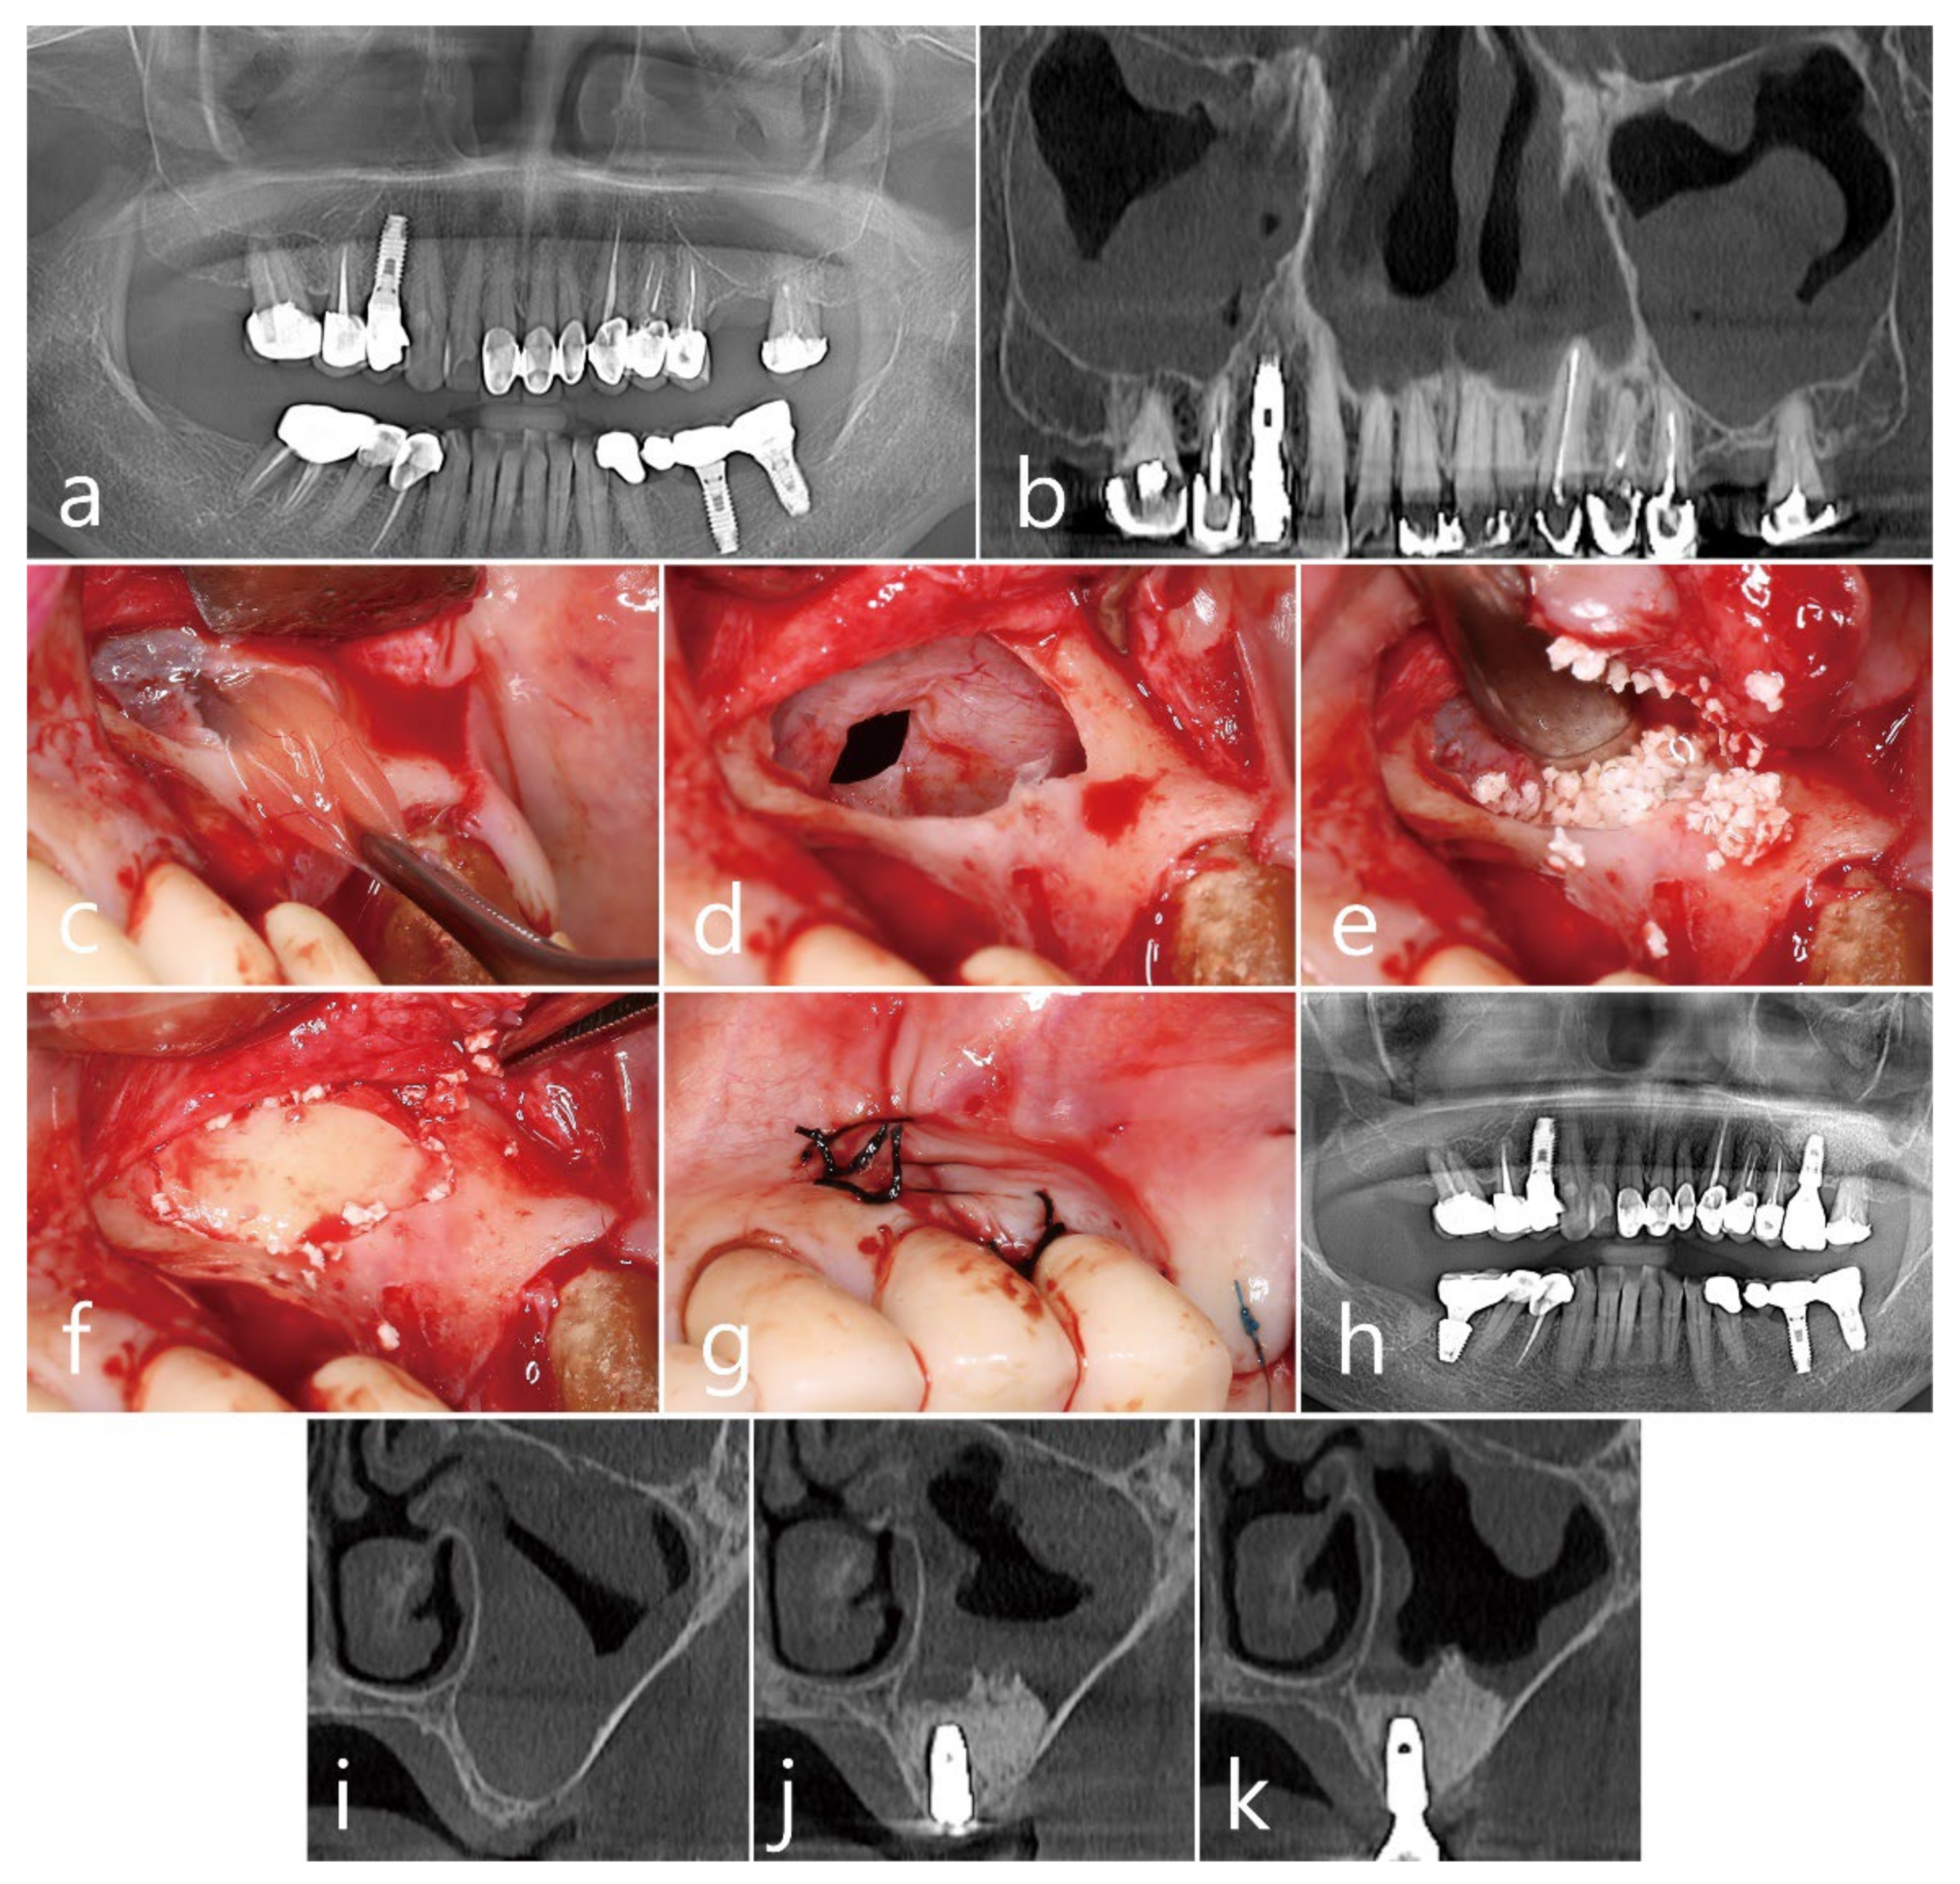

2.2. Case 2